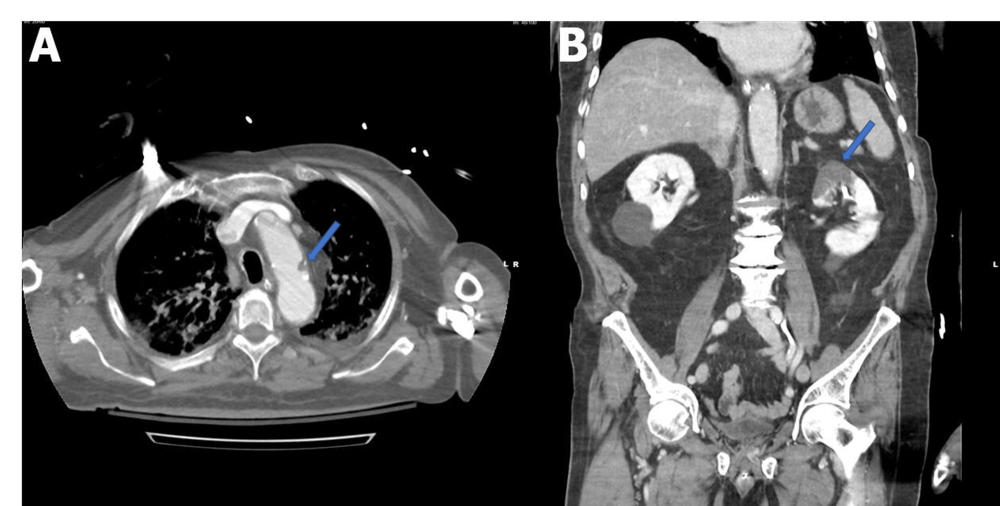

Figure 2. A, Axial contrast-enhanced CT of the chest demonstrates a filling defect in the aortic arch (arrow) consistent with thrombus. B, Coronal contrast-enhanced CT of the abdomen and pelvis demonstrates a wedge-shaped low-attenuation region in the superior pole of the left kidney (arrow) consistent with renal infarct. (Lushina, et al.)

High-res (TIF) version